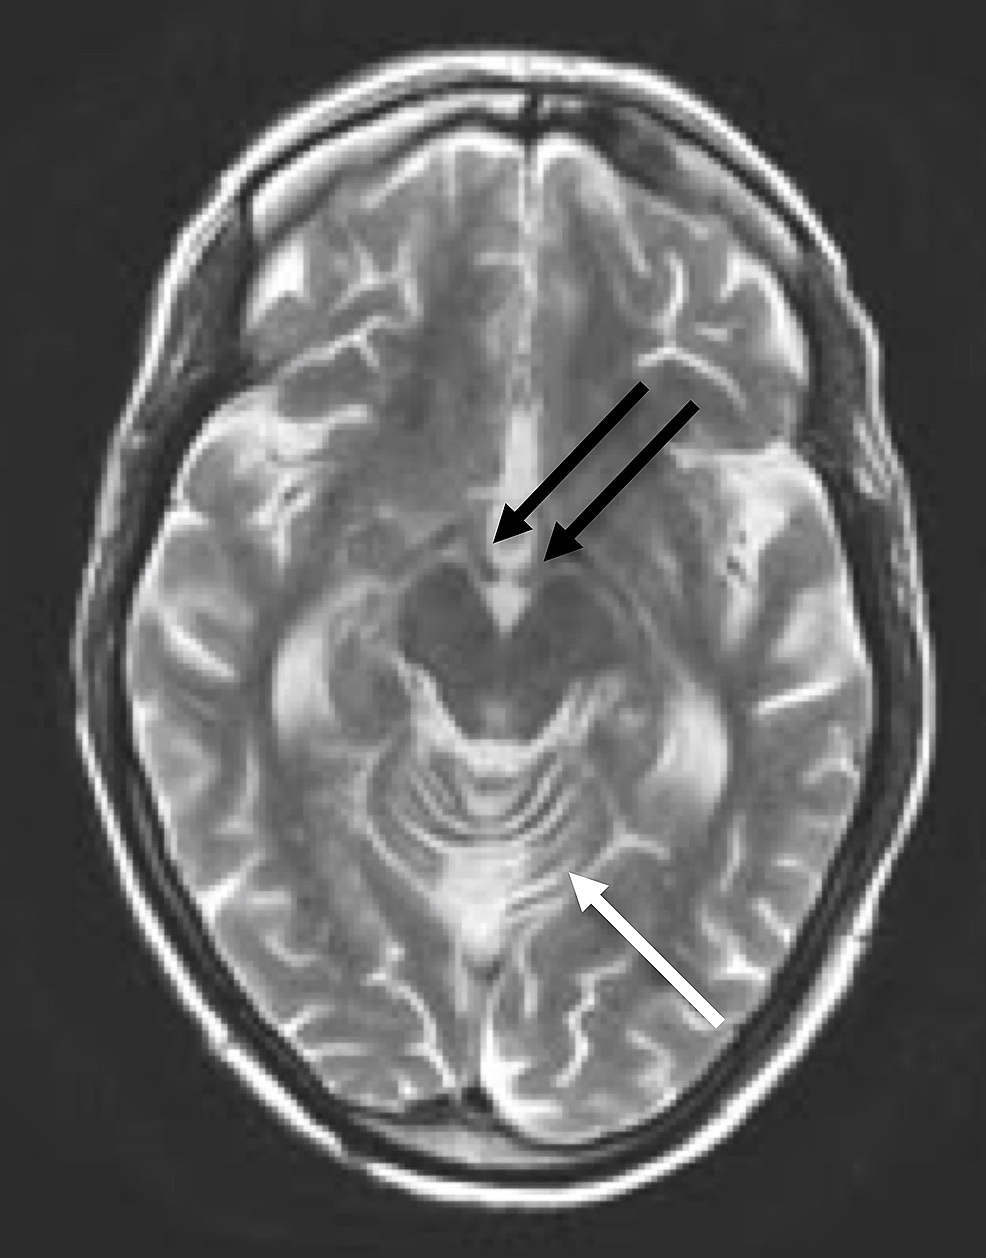

MRI of her brain demonstrated cerebellar volume loss, increased FLAIR signal in the cerebellar vermis, normal corpus callosum and normal mammillary bodies (Figures 2-7).

Although not required for a diagnosis of acute WE, “typical” MRI findings include hyperintense FLAIR/T2 signal in the thalami, mammillary bodies, tectal plate, periphery of the third ventricle, and periaqueductal area [3,6]. Approximately 50% of patients with WE exhibit “atypical" MRI findings including FLAIR/T2 hyperintensity in the superior cerebellum, cranial nerve nuclei, red nuclei, dentate nuclei, caudate nuclei, splenium, and cerebral cortex [6]. Historically, these “typical” findings were thought to be more associated with alcoholics while the “atypical” findings were more associated with non-alcoholics. However, recent literature suggests that “typical” and “atypical” findings are less closely linked to alcohol-related and non-alcohol related WE than previously reported, as in our patient with alcohol-related WE displaying only “atypical” MRI features [7]. Differential diagnosis in patients with MRI findings of WE would include arterial/venous infarction (expected to show restricted diffusion), viral encephalitis (expected to have greater areas of increased FLAIR/T2 signal; atrophy would be unusual) and Marchiafava-Bignami Disease (expected to have callosal signal abnormality).